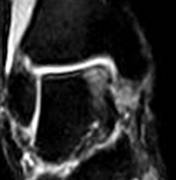

При МР-томографии интенсивность сигнала задней малоберцово-таранной связки повышена на Т2 ВИ, контуры прерывисты.

| Рис 2. Аксиальная и коронарная плоскости сканирования. Т2 ВИ. Стрелкой показан полный разрыв задней малоберцово-таранной связки. В коронарной плоскости (б) можно лишь предположить наличие повреждения, а на аксиальной (а) это полностью подтверждено. | ||||